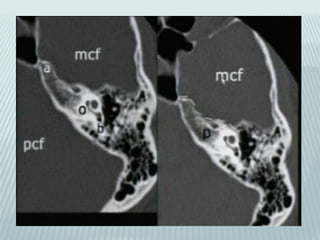

Petrous and its subsegments

•Pyramid and otic capsule

•Subsegments

1. Anterior

2. Posterior

3. Inferior

4. Apical

Posterior petrous subsegment

Inner acoustic pore;

Inner ear canal joins SAS

Modiolus;

entrance to chochlea for

chochlear nerve

Posterior petrous aqueducts

Vestibular (endolymphatic):

parallel to petrous ridge

Cochlear (perilymphatic):

Verticaly below and parallel to

inner ear canal